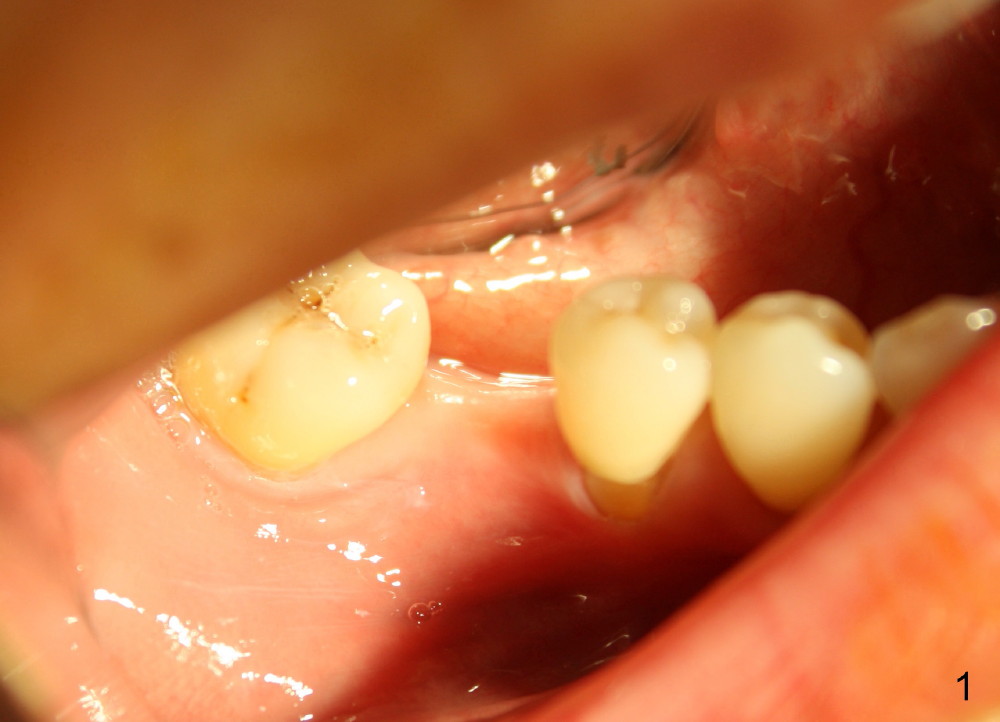

The ridge of the lower right molar is narrow buccolingually (Fig.1). After incision, ridge split is finished with a surgical fissure bur (Fig.2,3).

The patient is scheduled to return for implant placement 3 weeks later. The red lines in Fig.4 (CT coronal section) represent bony cuts in the ridge. A transverse incision is made over the top of the ridge with minimal exposure of the ridge. A curved osteotome is inserted into the upper bony cut (Fig.5). As the chisel is tapped in, the buccal segment moves buccally (Fig.6 pink arrow). When the chisel is withdrawn, a pilot drill is used to initiate osteotomy (Fig.7). As drills increase in diameter, the buccal segment continues moving buccally (Fig.8). Finally a bone-level implant (4.1 or 4.5x12 mm, Fig.9) or sub-crestal implant (4 or 4.5x8) is placed. Will the ridge split work?